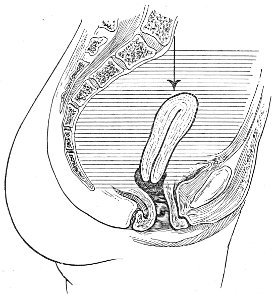

Vaginal and Bimanual Examination.—Having examined and noted the condition of the external genitals, the physician should next proceed to examine the vagina. The index finger of the right or the left hand should be gently introduced into the vagina. The condition of the vaginal walls, and the direction, consistency, form, etc. of the vaginal cervix, may be determined. The shape and size of the os uteri should be noted. The ulnar edge and the tips of the fingers of the other hand should then be placed upon the abdomen, immediately above the symphysis pubis, and gently pressed backward and downward toward the vaginal finger 24 (Fig. 2). In this way the various pelvic organs, the uterus, Fallopian tubes, ovaries, and ureters, may be palpated between the two hands, and their position, size, shape, and consistency may be determined. Such an examination is, of course, made much more easily in a thin woman than in a fat one. A thin woman a few weeks after labor may be examined most easily, on account of the relaxation of the abdominal and vaginal walls.

Fig. 2.—Bimanual examination.

In making the bimanual examination the structures 25 should be palpated methodically in order. The vaginal finger notes the condition of the cervix uteri. If the fundus be in the normal position, the uterus can then be taken between the abdominal hand (upon the fundus) and the vaginal finger (upon the cervix) (Fig. 3). The shape, size, mobility, and consistency are noted. The vaginal finger is then passed anteriorly and laterally toward either uterine cornu, while the abdominal fingers pass over to the posterior aspect of the same cornu. The ovarian ligament and the proximal end of the Fallopian tube may thus be felt. Passing farther outward, the whole of the tube and the ovary may be examined. The same procedure is then applied to the opposite side.

Fig. 3.—Bimanual examination; median sagittal section of the pelvis.